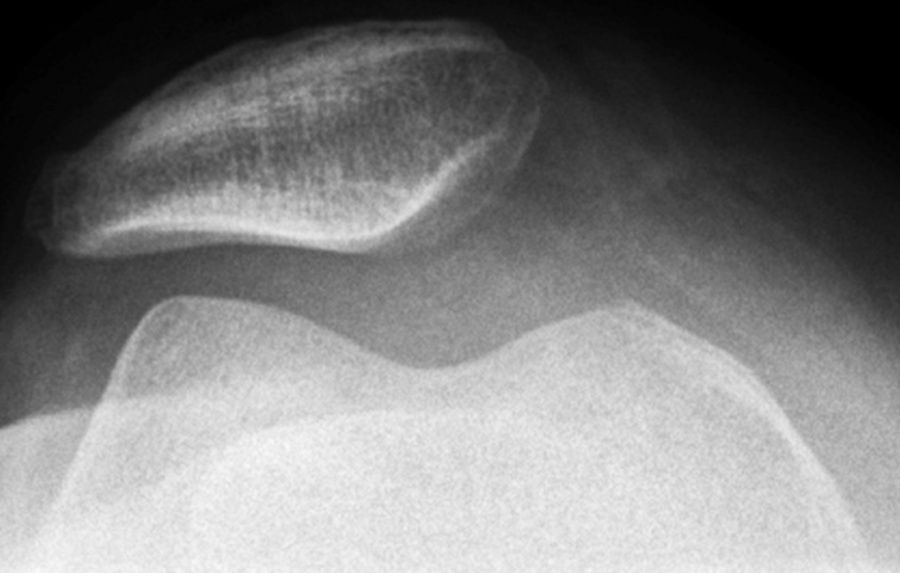

Das Patellofemoralgelenk (Kniescheibe - Patella; Oberschenkel - Femur) wird von der Patella und dem Gelitlager des Femur gebildet.

Die Hauptursache der Beschwerden besteht häufig in einer Fehlstellung der Kniescheibe (Dezentierung). Durch die schlechte Zentrierung kann es einerseits zu einer Fehlbelastung der stabilisierenden Weichteile, andererseits infolge der ungleichen Belastung des Knorpels der Kniescheibenrückfläche zu Belastungsschmerzen kommen. Diese können auch durch einen Knorpelschaden oder durch eine Arthrose verursacht sein.

Eine vorliegende Luxationstendenz mit eventuell auftretenden vollständigen Luxationen stellt aufgrund der vielfältigen Ursachen eine besondere diagnostische und therapeutische Herausforderung dar.